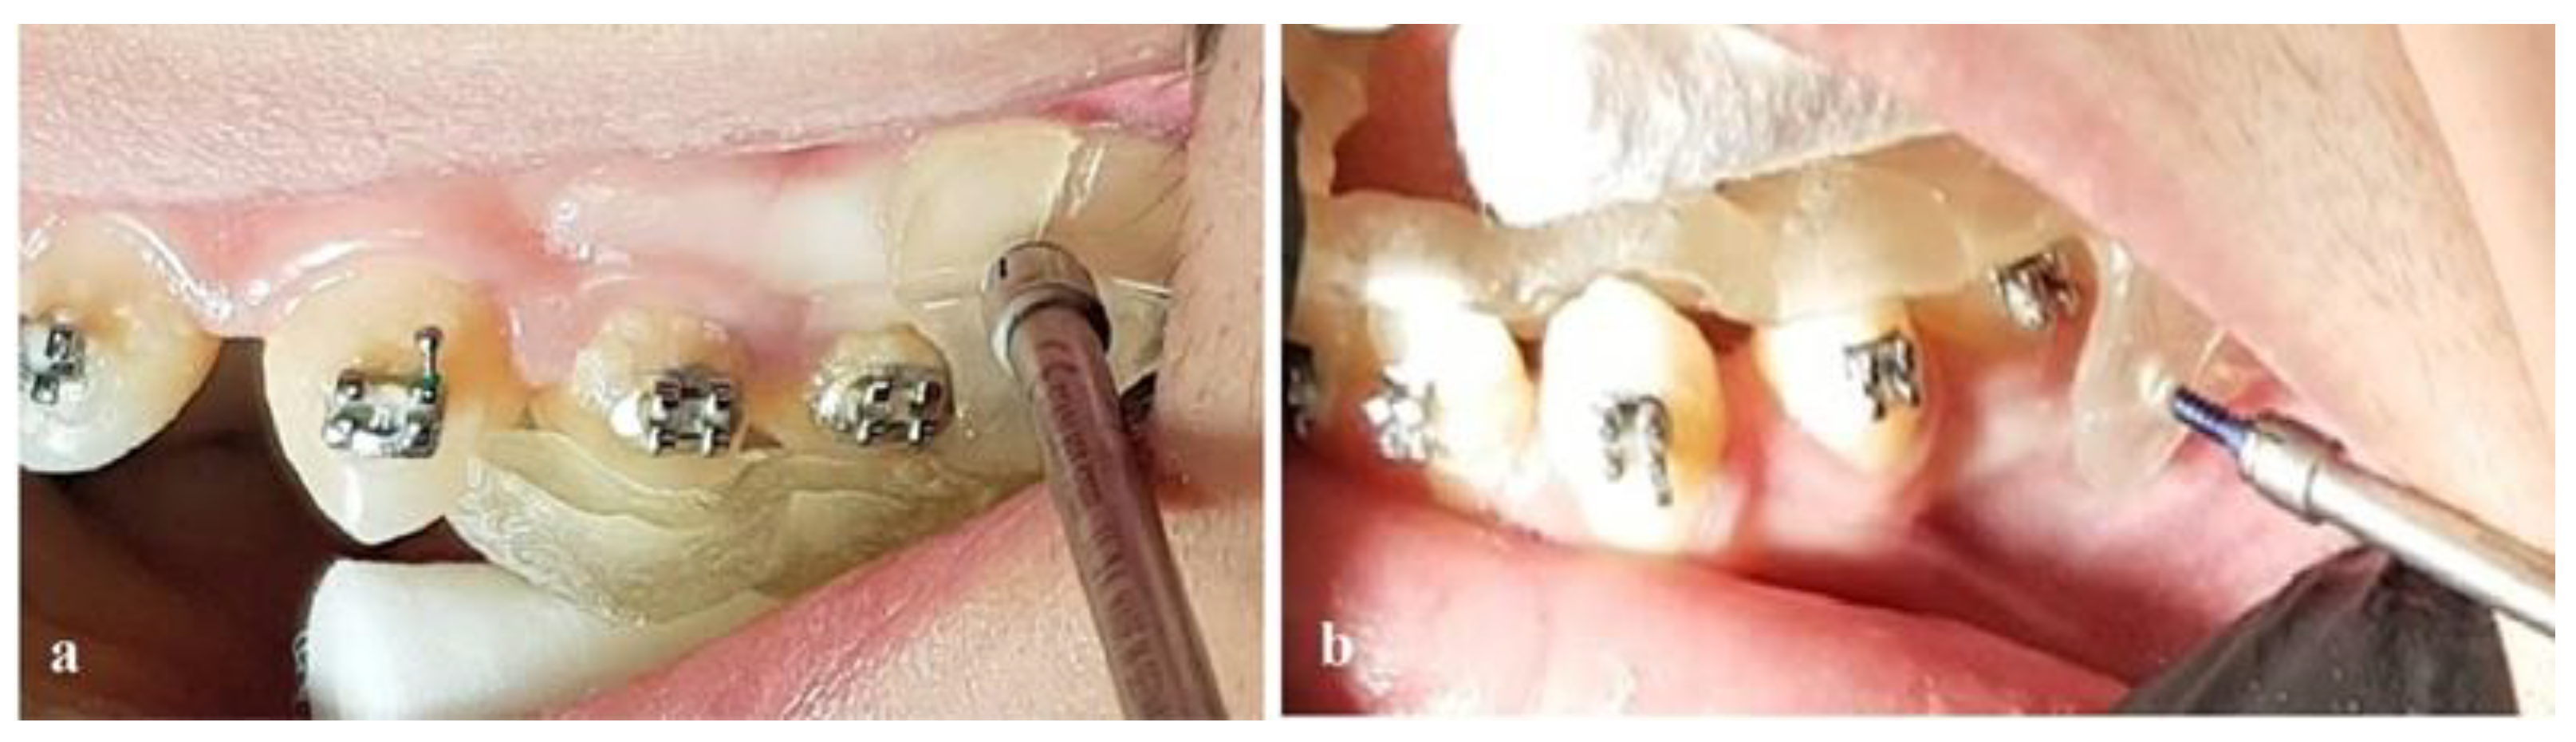

Bimaxillary Dentoalveolar Protrusion Case Treated with Anchorage by Buccally Implemented Mini-Implants Using a 3D-Printed Surgical Guide

2. Materials and Methods